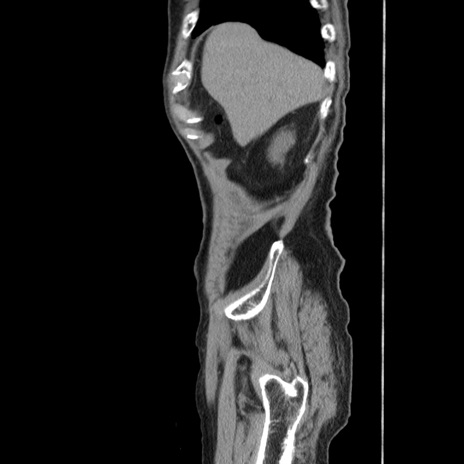

症例24(矢状断像)

【症例】80歳代男性

【主訴】左側腹部痛、嘔吐

【現病歴】本日早朝より左腹部に痛みあり。昼頃嘔吐認めたため、救急要請。

【既往歴】直腸癌(Mile手術)、胆摘

【身体所見】意識清明、BT 35.9℃、BP 221/93mmHg、SpO2 97%(RA) 、腹部:左ストーマ周囲に限局性の腹部膨隆あり。 膨隆部自発痛・圧痛あり・軟。

【データ】WBC 7700、CRP 0.09